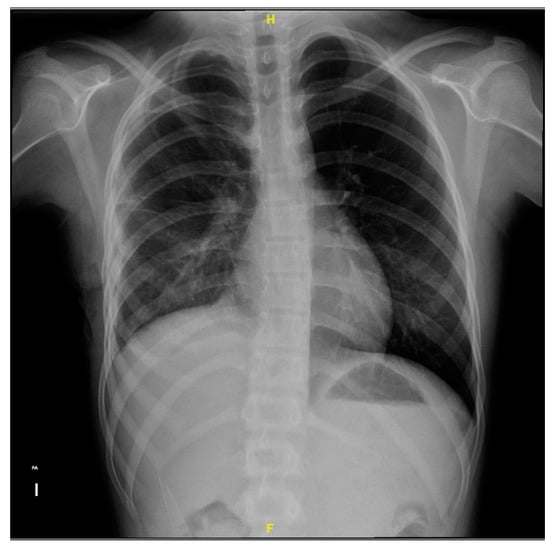

Upon admission to the emergency department of our hospital, she scored 15 on the Glasgow scale, requiring oxygen support with a face mask at 10 L/min, presented polypnea, the right hemithorax amplexation was decreased, and oxygen saturation of 89%. In addition, the right pleural tube showed 370 mL of hematopurulent output with a total of 128 mL (2.9 mL/kg/h) in 24 h. The gasometric study at the intake showed acid–base balance, hypoxemia, and normolactatemia (Figure 1).

Figure 1. Anteroposterior thoracic X-ray taken on admission shows a right pleural tube and right pleural effusion with loss of the costophrenic angle and radiopacity in the right lung.